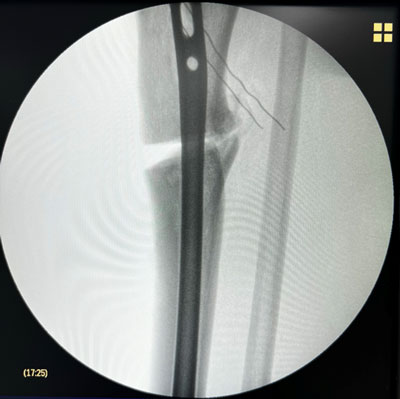

Management of a post-traumatic knee pain: Intra-operative images

Intra-operative images